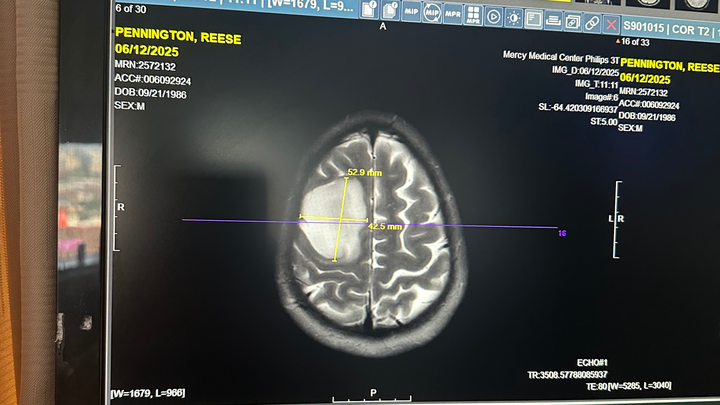

Reese was recently diagnosed with a Grade 2 Oligodendroglioma — a rare, slow-growing but serious primary brain tumor. It’s something no one ever expects to hear, especially at just 38 years old.